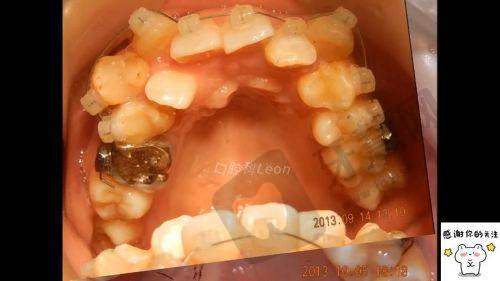

厦门小贝壳口腔门诊部顾客实例

厦门小贝壳口腔门诊部口碑良好,患者对其服务体验、性价比和技术都给予了高度评价。以下是两则顾客实例: